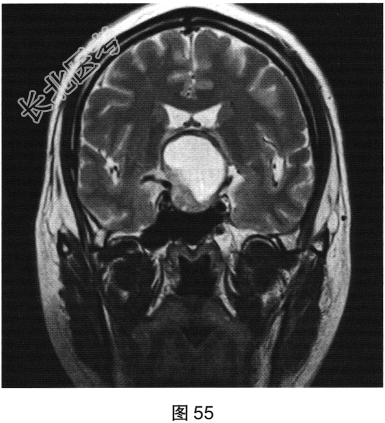

- 多项选择题2.[提示]患者行垂体MRI检查,见图55~图59。患者MRI检查可见哪些阳性影像学表现( )

A、矢状位增强扫描显示垂体及垂体柄显示不清

B、冠状位T1WI上呈等高信号

C、矢状位T1WI上视交叉抬高

D、冠状位T2WI上呈等高信号

E、矢状位T1WI上垂体显示不清

F、冠状位T1WI上可见钙化信号影

G、冠状位增强扫描显示实性部分明显均匀强化

H、MRI示鞍区囊实性占位性病变

I、冠状位增强扫描显示双侧海绵窦受侵